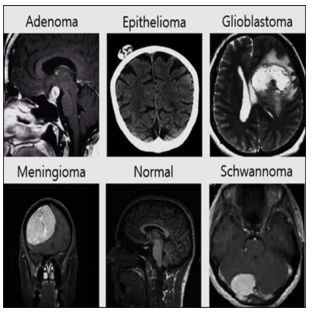

The data set for the study consisted of 414 primary brain tumor MR images of 86 adenomas, 84 epithelial tumors, 82 glioblastomas, 80 meningiomas, 82 schwannomas, and 39 normal MR images, for a total of 453 images. The images were collected from GitHub and NEJM [10], Auntminnie [11], Medscape [12], Radiology cases [13], and radiopaedia [14] sites, labeled by brain tumor, and organized into a file named ‘BrainTumors_1.1.zip’.

Fig. 1. Part of the MR images of brain tumors for the experiment (Adenoma, Epithelioma, Glioblastoma, Meningioma, Schwannoma).

Fig. 1 shows a portion of the MR images of Adenoma, Epithelioma, Glioblastoma, Meningioma, and Schwannoma brain tumors constructed for the experiment.